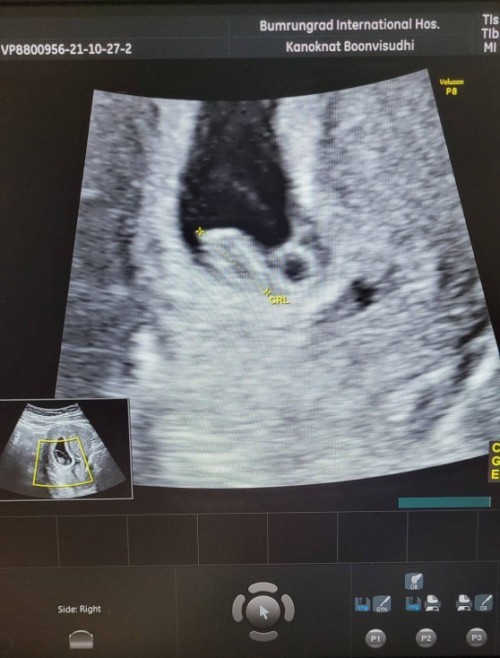

ซาวมาเมื่อวานคะ 7w หัวใจเต้นแล้ว ท้องแรกคะแต่รอบที่4 ลุ้นมากว่าน้องจะไปต่อกะแม่ไหม....

7 วีคค่ะ ได้ฟังเสียงหัวใจ แล้วก็เจอน้องแล้วจ่ะ ตอนแรกแอบลุ้นเหมือนกันว่าจะเจอไหม🥰

รูปนี้คุณแม่ท้องได้ 7 วีค 4 วัน ค่ะ ได้ฟังเสียงหัวใจและเห็นขนาดตัวของน้องชัดเจนค่ะ

7w ค่ะ ซาวด์ทางช่องคลอด เพราะซาวด์ทางหน้าท้องไม่เจอน้อง น้องแอบหลบมุม